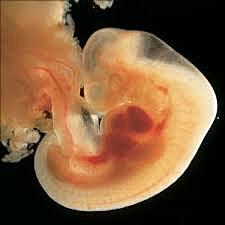

TERCERA SEMANA

• Gastrulación

11

Gastrulación

El disco bilaminar se transforma en trilaminar (ectoderm, mesodermo, endodermo)

• Nerulacion

12

Nerulacion

Formación del tubo neural que formara el sistema nervioso central

13

Formación de la resta neural, que migraran por el resto del cuerpo y formaran tejidos especializados

• Desarrollo de somitas

14

Desarrollo de somitas

Son bloques de independientes del mesodermo que darán origen a celulas que formaran, vertebras, costillas, y piel